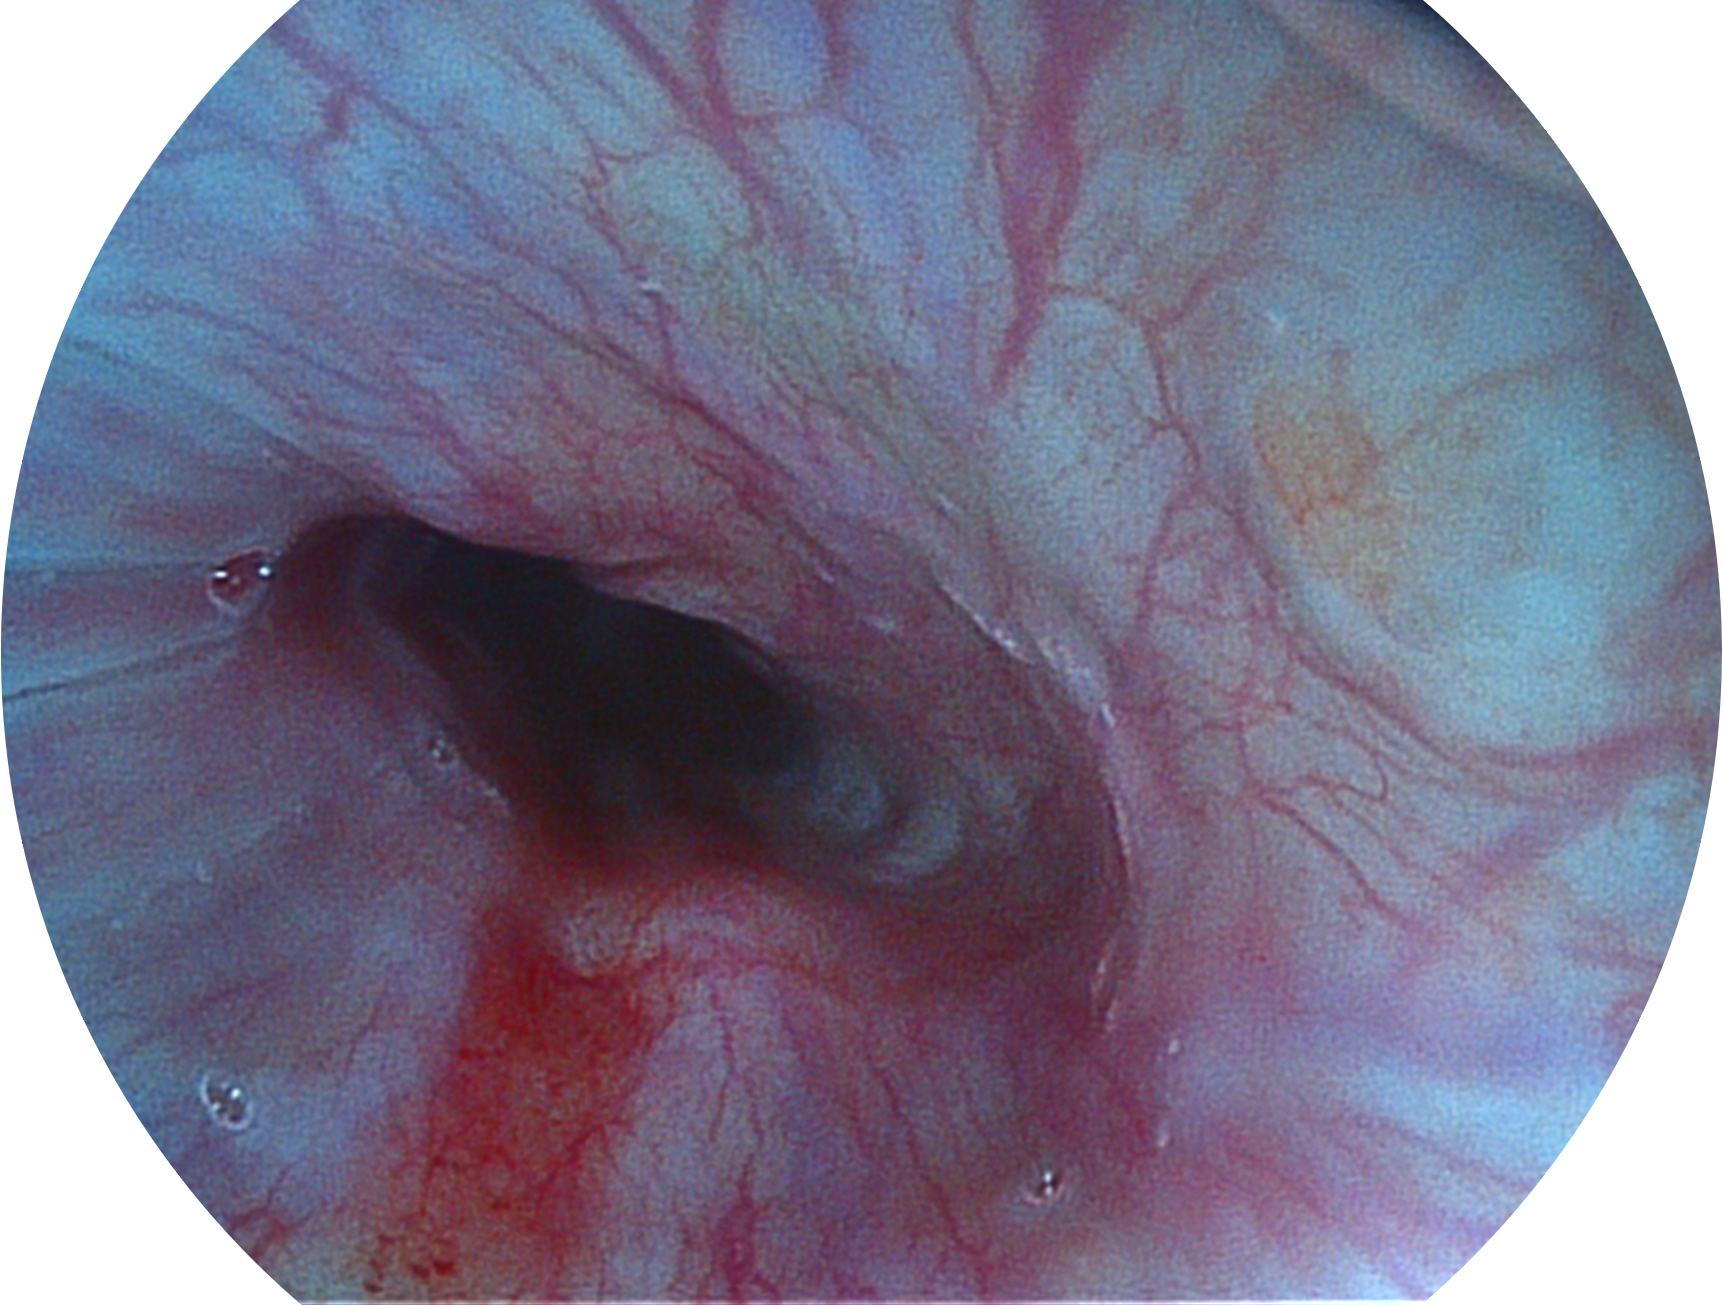

開立新開發(fā)的內(nèi)鏡染色技術(shù),主要是基于多波長(zhǎng)LED 光源的開發(fā),VLS-55Q 四波長(zhǎng)LED 光源是由四個(gè)不同顏色的LED光按照相應(yīng)照明模式所規(guī)定的特定發(fā)光比例進(jìn)行合束后形成,合束后形成的照明光的光譜由紅光、綠光、藍(lán)光及藍(lán)紫光這四個(gè)不同的波段范圍構(gòu)成。具有更高光譜自由度,通過光譜比例的控制,實(shí)現(xiàn)了聚譜成像技術(shù),英文全稱為“Spectral Focused Imaging, SFI”,縮寫為“SFI”和光電復(fù)合染色成像技術(shù),英文全稱為“Versatile Intelligent Staining Technology, VIST”,縮寫為“VIST”。